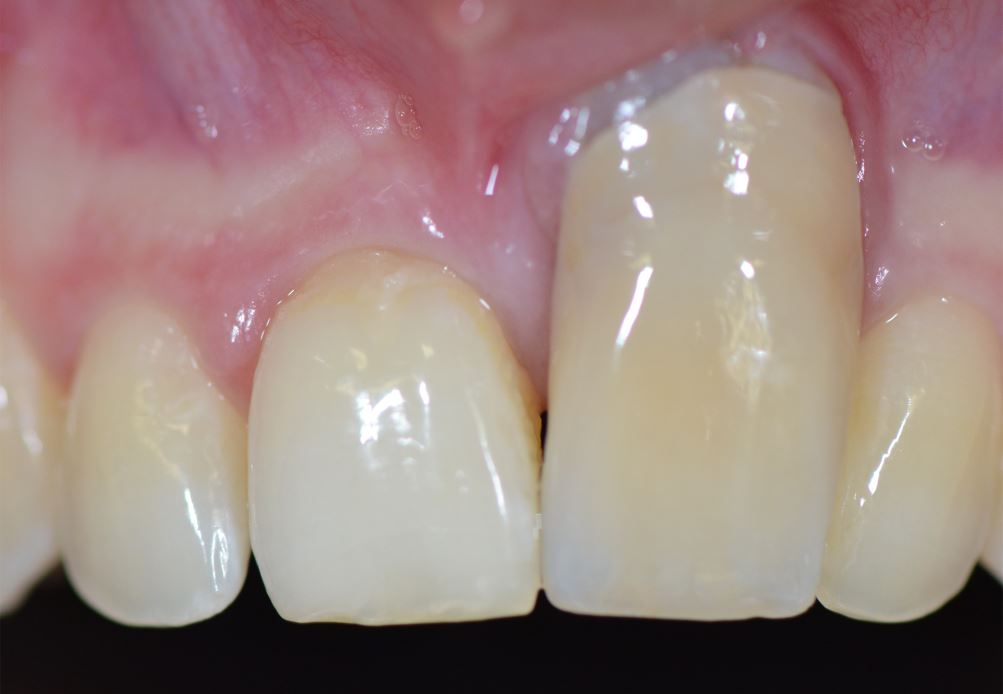

Abb. 3a

Zustand nach Frontzahntrauma mit nachfolgender prothetischer Versorgung im Wechselgebiss vor ca. 10 Jahren.